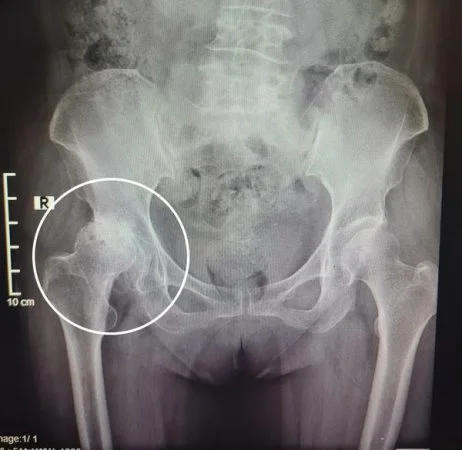

Hoại tử chỏm xương đùi hay còn gọi là hoại tử vô mạch chỏm xương đùi, nguyên nhân do thiếu máu nuôi dưỡng. Dẫn tới tình trạng xương hoại tử tổ chức xương và sụn, lúc đầu vùng chỏm xương thưa dần, hình thành các ổ khuyết xương về sau dẫn tới gãy xương dưới sụn và cuối cùng gây ra xẹp chỏm xương đùi, mất chức năng khớp háng dẫn đến tàn phế.

Hạn chế vận động khớp háng đau xuất hiện làm vận động khớp háng khó nhất là động tác xoay trong, xoay ngoài, dạng và khép. Người bệnh thường khó khăn trong việc ngồi xổm hoặc không thể ngồi xổm được.

Đến giai đoạn sau người bệnh đau tăng nhiều, hạn chế hầu như các vận động khớp háng bao gồm cả động tác gấp, duỗi.